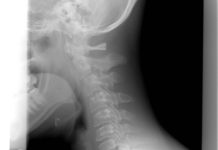

Wysłali go do domu ze złamanym kręgiem szyjnym

41-letni John Barnet po wypadku motocyklowym miał złamania mostka i kręgu w odcinku szyjnym kręgosłupa. Przez sześć godzin przebywał Dr. Everett Chalmers Regional Hospital...